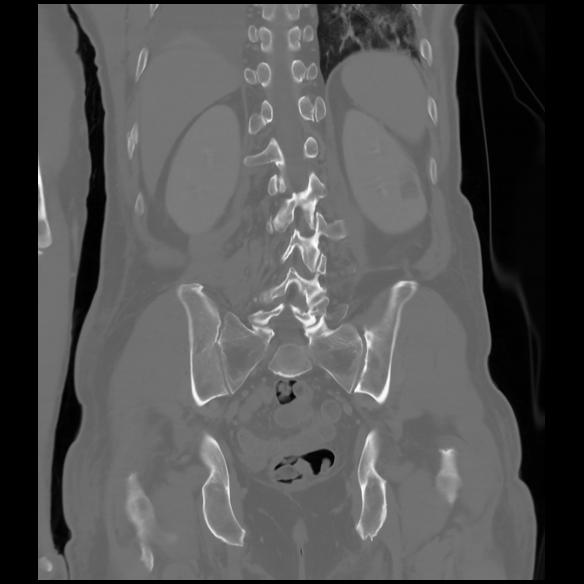

6 CUERPO,CE,Coronal,3.000,CUERPO,Coronal,